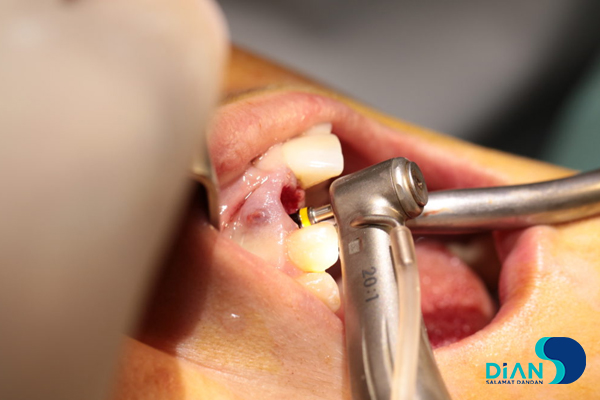

Under local anesthesia of DS-Forte articaine 4% the dentist made syndesmotomy and removed artificial tooth crown.

The root of the tooth root was divided into vestibular and palatal fragments.

In the process of vestibular root fragment extraction the dentist found its interlocking with alveolar socket. There was a risk that a root fragment would break off with a part of alveolar socket. It was decided to apply «Socket shield» technique. The palatal root fragment was removed.

Then the dentist polished remained root part and conducted alveoli curettage.